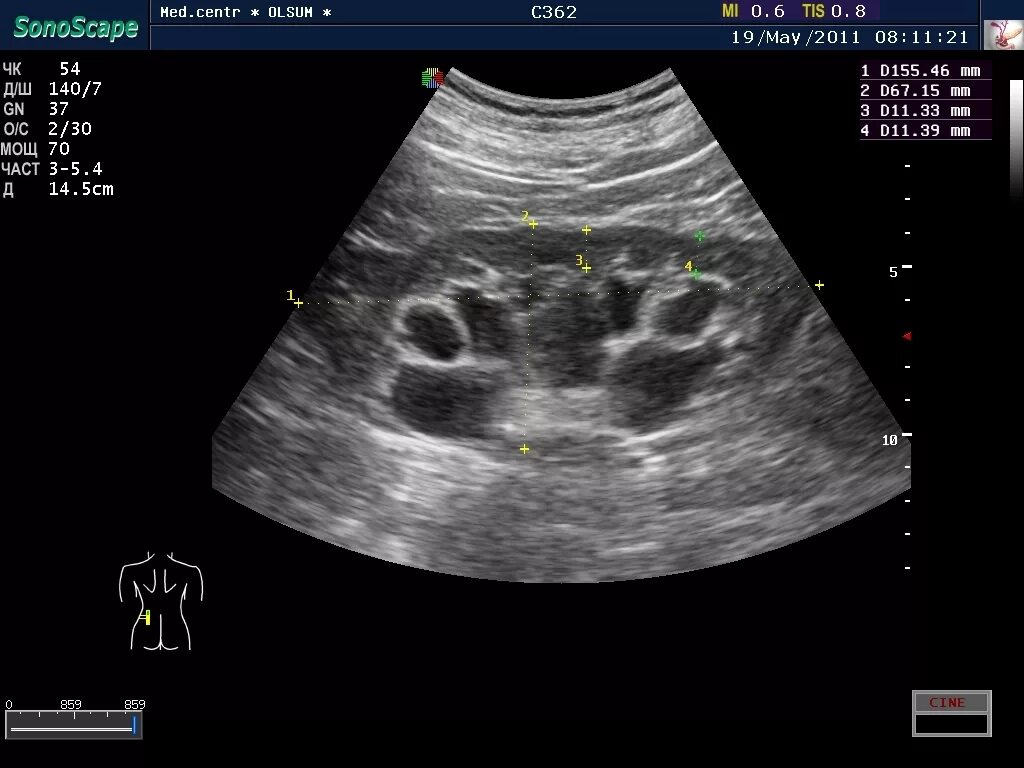

Узи сердца узи почек